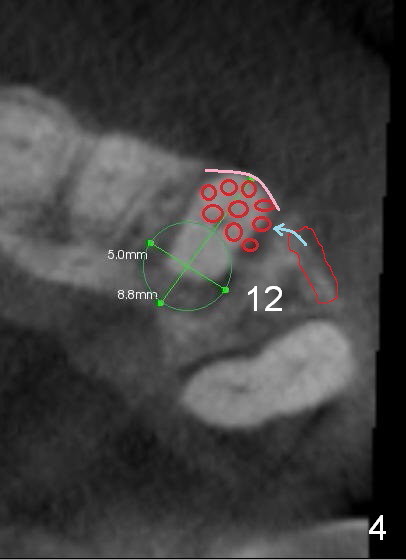

A 65-year-old man has history of Type II diabetes and stroke. He is taking a blood thinner (Xarelto 20 mg qd). The tooth #11 has been mobile for several years. Fig.1 is a CBCT taken 2 years 8 months earlier. The affected tooth has now supraerupted (Fig.2 arrow) with apical abscess (arrowhead).

Bone defect at present should be more severe than CBCT coronal (Fig.3) and axial (Fig.4) sections indicate. After palatal placement of a 5x20 mm tissue level implant (Fig.3 green area) and an appropriate abutment, an immediate provisional is to be fabricated. A block graft is harvested from #12 edentulous region (buccal plate) to the buccal defect at the site of #11 (Fig.4 curved light blue arrow). Prepare surgical handpiece and chisels. The remaining bony defect will be filled with allograft and Osteogen (red circles). The graft site is going to be covered by Osteotape (Fig.3,4 pink curved line), while the donor site is given mixture of allograft and Osteogen and Collagen Dressing. When the soft tissue deficiency is found, connective tissue graft is to be harvested from the palate. If visibility is compromised for these steps, an incision will be made as shown in Fig.5. This should be done with caution considering the medical conditions. Before surgery, ask the patient whether the blood thinner has stopped for a few days or not and how diabetes control is.